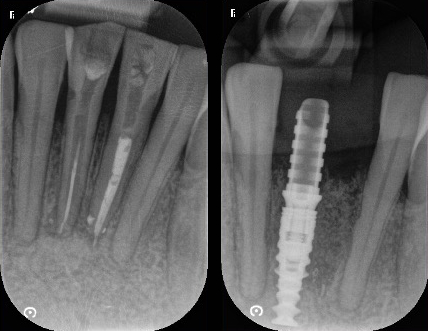

Cas esthétique d'implant unitaire

Mise en charge immédiate

Avec un implant unitaire et la mise en charge immédiate dans les zones esthétiques (quand c’est possible et selon le cas observé), la phase de cicatrisation, normalement de quelques semaines, se déroule avec une dent provisoire fixe (couronne provisoire vissée) qui permet d’éviter l’installation d’une prothèse provisoire amovible (dentier). Cela épargne aux patients de subir une intervention supplémentaire et il s’agit aujourd’hui d’une procédure standardisée, très confortable et très appréciée par les patients. C’est uniquement dans les cas exceptionnels, comme par exemple en cas d’infections aiguës, qu’il est préférable d’extraire d’abord la dent délabrée et de poser l’implant seulement lorsque l’inflammation est résolue.